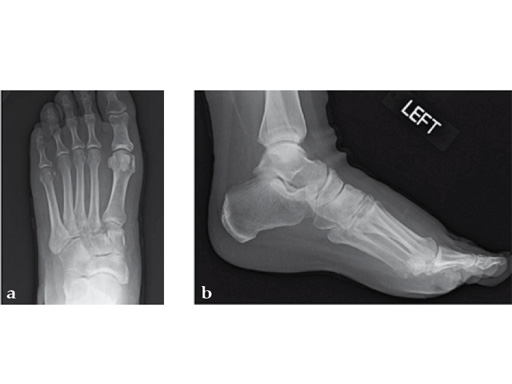

Case 7: VA -locking X-plate

A 49-year-old woman had extreme pain in the talonavicular joint.

Case provided by Andrew Sands, New York, New York, USA

As isolated fusion of the talonavicular joint is often hard to achieve, a 4.0 mm lag screw a plus X-plate was used (see Fig. 2a-c).

Fusion of the talonavicular joint while saving the rest of the hindfoot complex motion was achieved (see Fig. 4a-c).